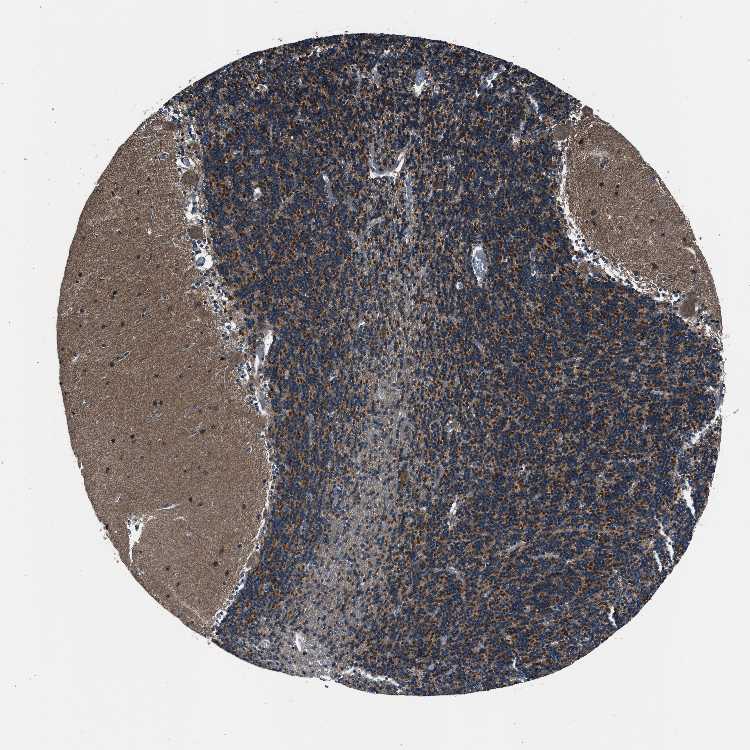

BRAIN CEREBELLUM Show tissue menu

CEREBELLUM - Expression summary

CEREBELLUM - Antibody stainingi

Antibody staining in the annotated cell types in the current human tissue is reported as not detected, low, medium, or high, based on conventional immunohistochemistry profiling in selected tissues. This score is based on the combination of the staining intensity and fraction of stained cells.

Each image is clickable and will lead to virtual microscopy that enables deeper exploration of all samples and also displays staining intensity scores, fraction scores and subcellular localization as well as patient and tissue information for each sample.

Antibody HPA011026Antibody HPA012037Antibody HPA014658

Purkinje cells LowMediumHigh

Cells in granular layer HighMediumHigh

Cells in molecular layer Not detectedLowHigh